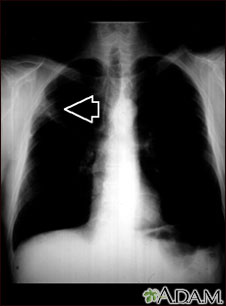

Radiografía del tórax de una persona con una masa pulmonar. Esta es una vista frontal, donde los pulmones son las dos áreas oscuras y el corazón y las otras estructuras son visibles en el centro del tórax. La radiografía muestra una masa en la parte superior del pulmón derecho, marcada por una flecha (al lado izquierdo de la imagen).